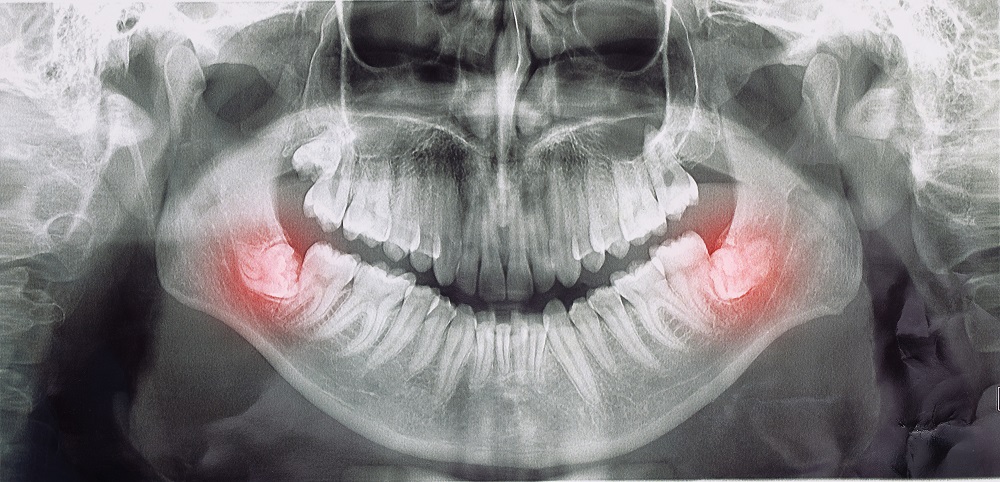

Usuwanie ósemek zaczyna się od procesu diagnostycznego, który pozwala dokładnie ocenić ułożenie zębów mądrości oraz ryzyko związane z ich zatrzymaniem. Wykonujemy zdjęcia RTG lub tomografię, dzięki którym widzimy położenie korzeni, sąsiednich zębów i struktur kostnych. Na tej podstawie wybieramy metodę: klasyczną ekstrakcję ósemek lub chirurgiczne usuwanie ósemek przy bardziej skomplikowanym ułożeniu zęba.